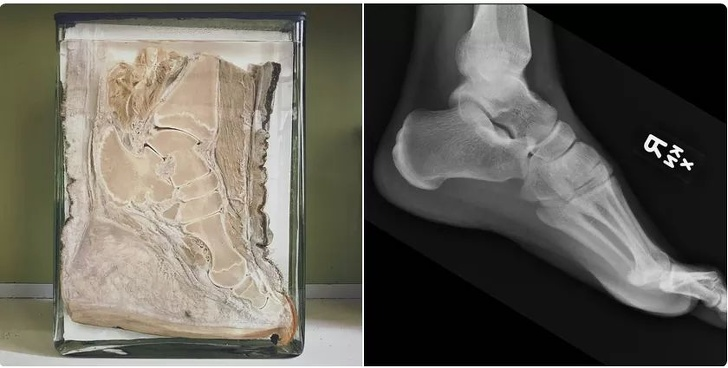

12. Đây là đôi chân của một người đã tham gia Tour de France, giải đua xe đạp nổi tiếng thế giới.

![]() |

| Ảnh: BrightSide |